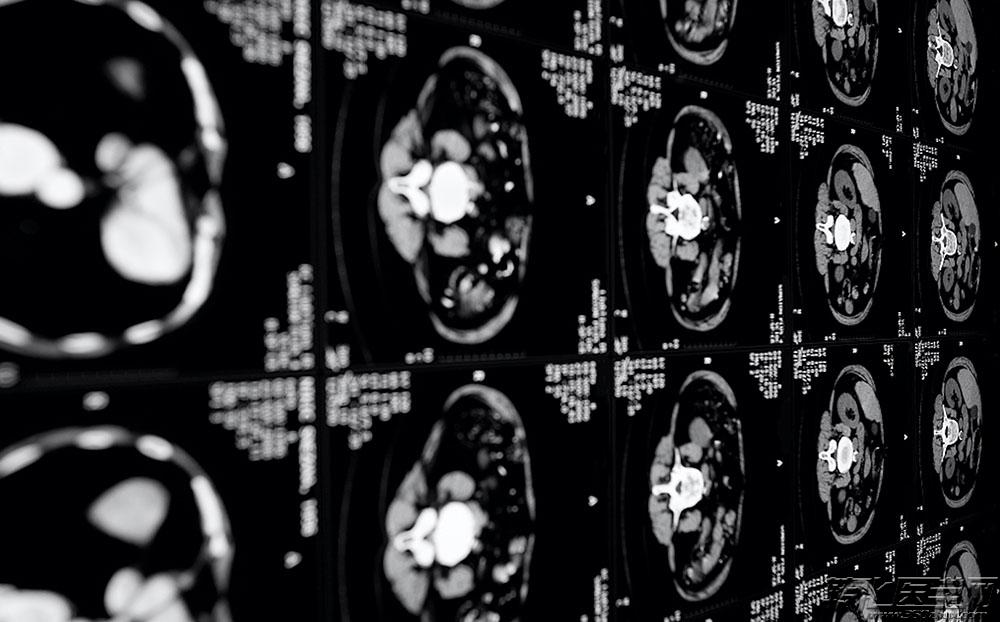

| 导读 | 据不完全统计,到2020年全球医疗数据量将达40万亿GB,其中80%以上是非结构化影像数据,这是“超级医生”需要挖掘的大金矿。是的,未来的影像医生需要挖掘大数据的能力。 |

广东省人民医院影像科主任刘再毅曾说,“我们数据多得不得了,我们影像科每天产生很多数据,但是有多少数据可以用?1%都不到,其中有大量错误信息。数据规范的问题没有办法管控,临床信息经常有误。”——这无疑就是国内医疗影像的现状。

据不完全统计,到2020年全球医疗数据量将达40万亿GB,其中80%以上是非结构化影像数据,这是“超级医生”需要挖掘的大金矿。

联合医生集团创始人林子洪医生在探访微软(中国)时表示临床数据最珍贵,光有技术没有临床数据,或只有临床数据没有技术,都是纸上谈兵。通过与微软的合作将云计算运用到医疗诊断中,为每一位影像医生配备人工智能武器,成为超级医生。学习到足够知识的计算机就可以在影像医生读片前提示图片中可能存在病灶的部分,提高影像医生读片的效率和准确性;在影像医生读片和做完诊断后,可以帮助检查是否有疏漏,并做出提醒。